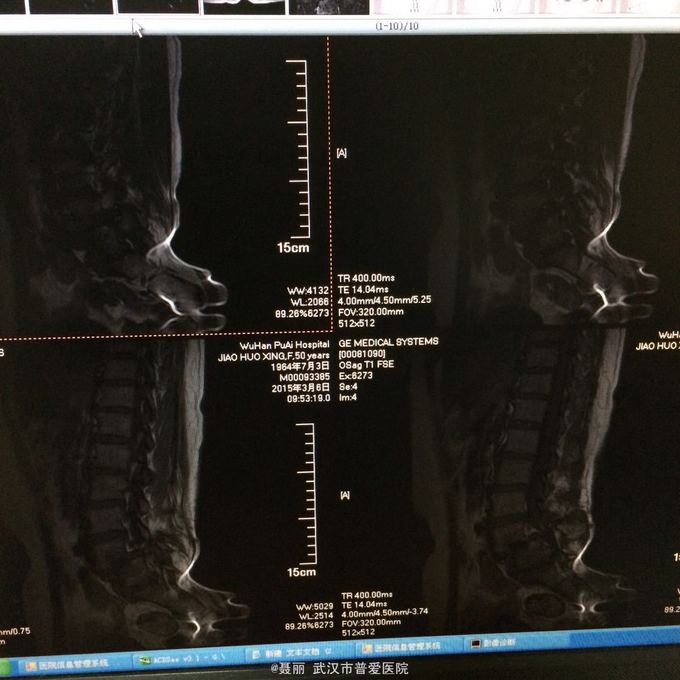

患者,女,51岁。 反复腰痛并间歇性跛行5年余,加重并左侧臀部2月余。 患者于5年前无明显诱因外伤诱因出现腰痛,不伴有双下肢麻木、乏力及间歇性跛行,卧床休息后好转,间歇发作,进行性加重。 既往史:有高血压病、糖尿病病史,否认有药物过敏

:L4/5棘突间轻压痛,叩痛,棘间左侧椎旁压痛;双下肢肌力、肌张力正常,病理反射未引出。 门诊资料:外院行腰椎CT检查示:L3-S1椎间盘膨出,L4椎弓崩裂并向前滑脱(重度)椎管狭窄。 入

入院诊断:、腰椎滑脱(L4/5 峡部裂性) 诊疗计划:1:完善有关检查2卧床休息,行改善微循环、3.腰椎后路复位减压植骨融合术

行改善微循环、3.腰椎后路复位减压植骨融合术 腰椎滑脱(L4/5 Ⅱ度)、腰椎管狭窄症(L3/4)、腰椎间盘突出症(L5/S1)查体双下肢感觉、活动无明显异常。双下肢末梢血液循环可。换药见伤口对合良好,无明显红肿渗出。伤口已拆线。嘱加强双下肢活动及功能锻炼,避免下肢深静脉血栓,主动及被动四肢活动,预防血静脉及床褥形成,加强腰背肌锻炼,适量康复功能锻炼。一个月后来复查伤口愈合好,疼痛没有,活动可